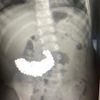

Hasil rontgen menunjukkan, magnet-magnet itu saling menempel dan membentuk empat garis lurus di dalam usus pasien.

Magnet tersebut bahkan menyebabkan beberapa bagian usus saling menempel karena gaya magnet.